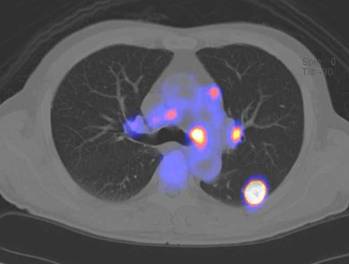

大腸がんの患者さんの実際の写真を示します。図1のPET画像では、腫瘍の活動性がよくわかります。図2のCT画像では、腫瘍の形がわかりますが、これだけでは診断は難しい像です。図3のPET-CT画像では、腫瘍の形と活動性が両方ともわかり、自信を持って大腸がんと診断できます。

肺がんの患者さんの実際の写真を示します。図4、図5のPET-CT画像で、肺がんが小さいリンパ節に転移している様子が明瞭に示され、治療方針を立てるのに役立ちます。

![]() |

| 図 4 PET - CT 画像 | 図 5 PET - CT 画像 |